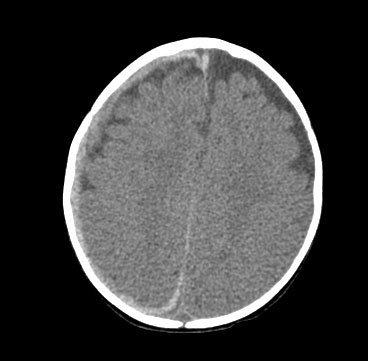

CT scan revealing subdural haemorrhage extending over the right convexity and in the intrahemispheric region, as well as enlargement of the extra-axial fluid spaces

From the personal collection of Alice Newton, MD; used with permission